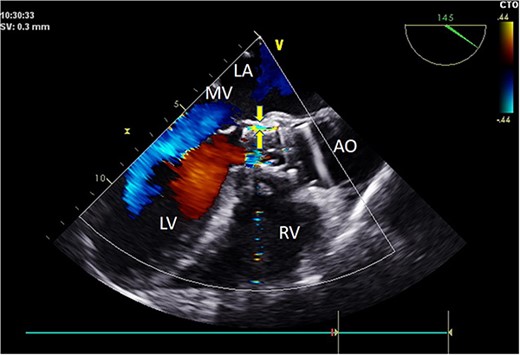

Intraoperatively, after self-expanding the aortic valve, TEE monitoring confirmed excellent cardiac function, disappearance of aortic valve regurgitation, secure anchoring of the aortic valve prosthesis, and no obstruction to the mitral valve leaflets or coronary ostia. The aortic valve velocity and pressure gradient upstream of the valve decreased compared to preoperative values, with a maximum velocity of 166 cm/s and a pressure gradient of 11 mmHg (Fig. 3). However, a periprosthetic leak with a residual width of ~4.5 mm was observed at the self-expanding valve’s interface with the native annulus (Fig. 4). Based on preoperative data, the decision was made to re-expand and reshape the prosthesis. Postdilation, TEE monitoring showed a reduction in the periprosthetic leak to 1.5 mm (Fig. 5), a significant improvement compared to predilation. Following satisfactory self-expansion results, the planned percutaneous ASD closure procedure was performed under ultrasound guidance. The closure device was securely positioned in the atrial septum, and TEE examination showed no deformation or impingement of the self-expanding valve (Fig. 6). Atrial shunting was eliminated, and the outcome exceeded expectations.

Intraoperative TEE: Long-axis aorta section shows a 1.5 mm-wide paravalvular blood flow beam, demonstrating significant improvement. Abbreviations: LA - left atrium; LV - left ventricle; RV - right ventricle; AO - aorta; MV - mitral valve.